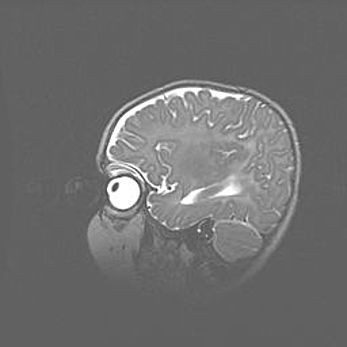

Подострая гематома правой гемисферы мозжечка.

Наружная гидроцефалия.

Возраст: 15 дней

Вес: 3100 г

Пол: женский

Окружность головы: 37 см

Срок гестации: 35-36 недель

При открытой наружной форме гидроцефалии у новорожденных расширяются и переполняются субарахноидные пространства.

Кровоизлияния в мозжечок имеют две клинико-анатомические формы: полушарные гематомы и кровоизлияния в червь.

К появлению этой патологии может привести: повреждения головного мозга, возникающие в результате асфиксии и гипоксии плода при беременности, или травмы во время родов. Редко гематома мозжечка может быть результатом первичной коагулопатии и сосудистой мальформации, диссеминированном внутрисосудистом свертывании, изоиммунной тромбоцитопении.